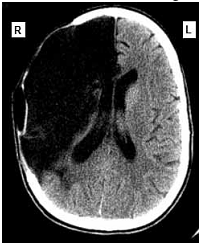

Uma mulher de sessenta e dois anos de idade foi levada pelo acompanhante ao atendimento médico de um hospital, às 7 horas e 30 minutos da manhã. O acompanhante relatou que a paciente tinha sofrido uma queda no banheiro de sua residência enquanto tomava banho, às 6 horas da manhã, e que ele a havia encontrado minutos depois. A paciente não conseguia mover o braço e a perna esquerdos, falava de forma lenta e arrastada, mas com sentido lógico. No exame clínico, foram observadas pressão arterial de 160 mmHg × 95 mmHg, ausculta cardíaca com ritmo cardíaco irregularmente irregular e frequência cardíaca de 98 bpm, sem sopros. A paciente estava com lentidão para responder a questionamentos, apresentava pupilas isocóricas e fotorreagentes, diminuição da sensibilidade dolorosa no lado esquerdo da face, paralisia facial central, hemiparesia flácida do hemicorpo esquerdo (mais acentuada nos membros superiores), reflexos profundos mais acentuados à esquerda e sinal de Babinski à esquerda. No eletrocardiograma realizado foram detectados ritmo de fibrilação atrial, com frequência ventricular média de 100 spm, SÂQRS = -30º, sinais de sobrecarga ventricular esquerda e alterações difusas e secundárias da repolarização ventricular. A tomografia computadorizada do crânio, sem contraste, realizada na paciente, apresentou o resultado mostrado a seguir.

Internet:<www.emedicinehealth.com> (com modificações).